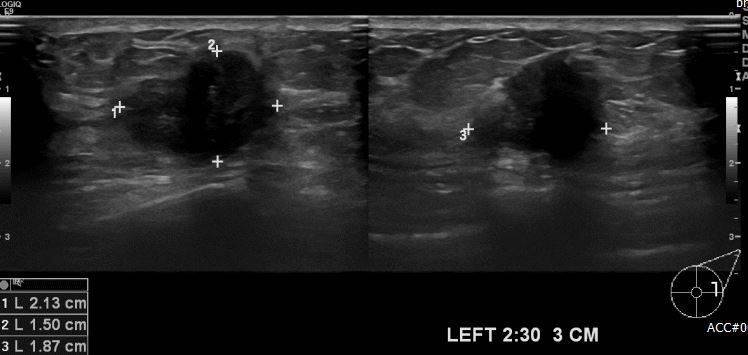

상기환자 좌측 유방에 만져지는 멍울로 내원하신 70대 여성분으로 좌측 2시 30분

방향 3cm 떨어진 거리의 만져지는 혹 조직검사 시행하여 좌측 침윤성 유관암 진단되었습니다.